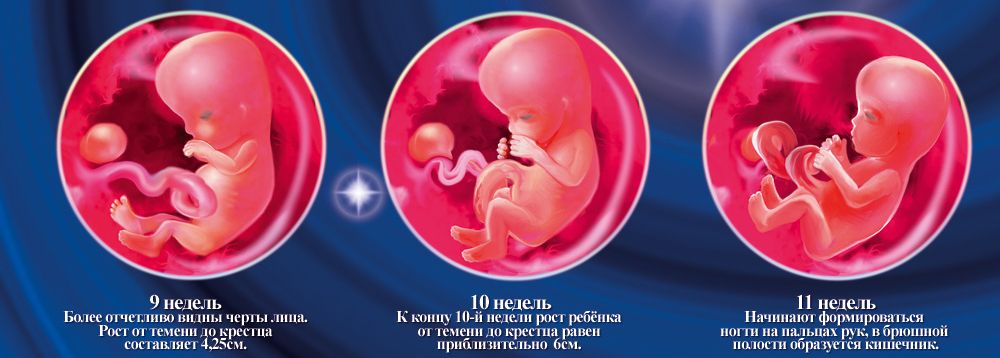

Этапы развития эмбриона человека: 14 недель